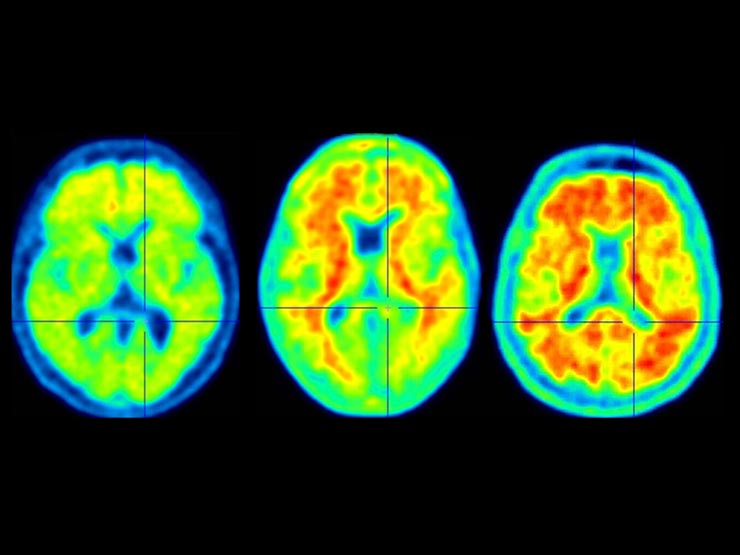

The causes of Alzheimer’s disease are not fully understood, but medical professionals believe that the condition may be due to genetic, lifestyle, and environmental factors. No matter what the cause, Alzheimer’s disease involves a loss of brain tissue.

Nerve cells, called neurons, connect to transmit information to and from the brain. In people with Alzheimer’s disease, proteins build up and form structures that disrupt communication between neurons in the brain. This causes the neurons to die and the brain tissue to deteriorate.